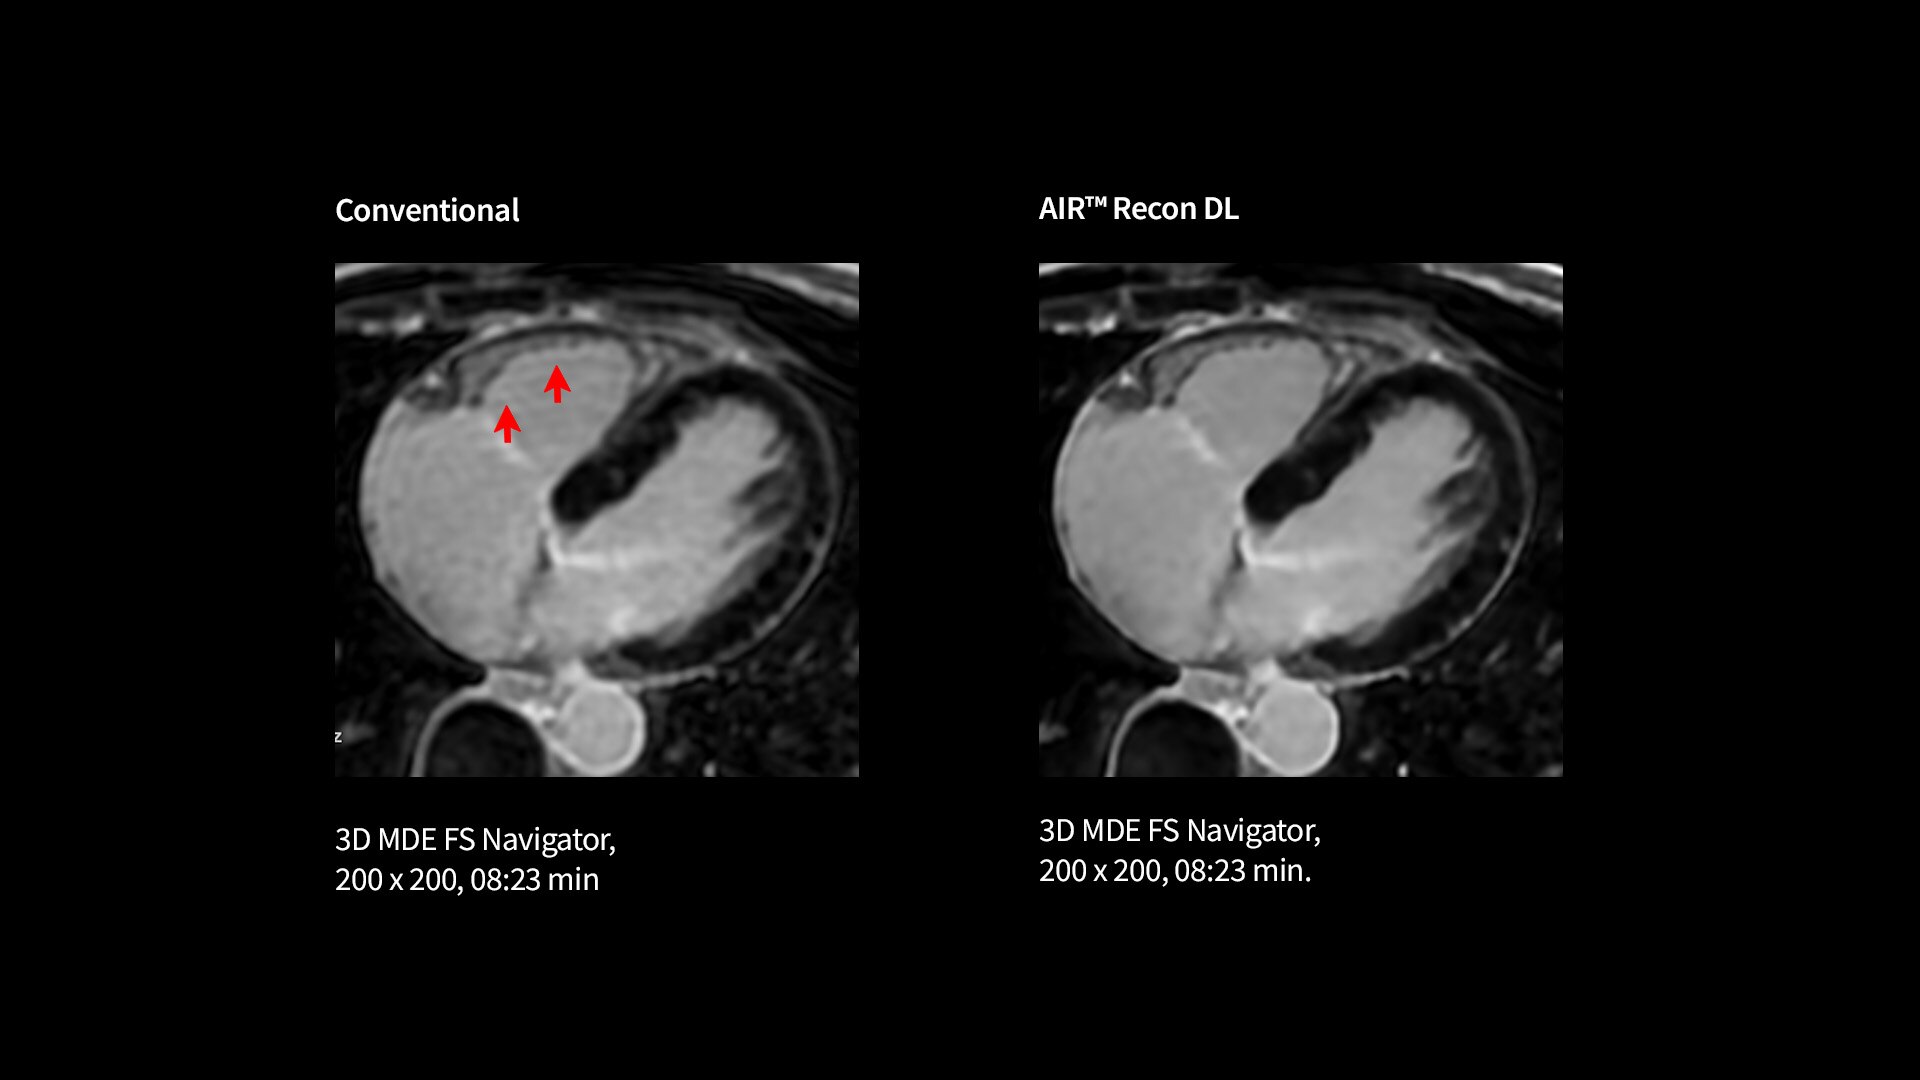

Improve SNR and image sharpness by up to 60% with AIR™ Recon DL

Your teams can capture clarity with AIR™ Recon DL, a revolutionary technique to boost image quality, providing accurate anatomic information and advanced soft tissue contrast. It’s already transformed the lives of millions of patients worldwide since 2021. Thanks to Sonic DL™ they can also now assess cardiac viability faster than ever before, with as little as 15 to 20 minutes per scan.*†